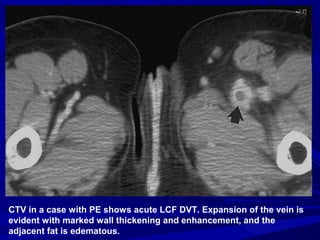

CTV in a case with PE shows acute LCF DVT. Expansion of the vein is

evident with marked wall thickening and enhancement, and the

adjacent fat is edematous.